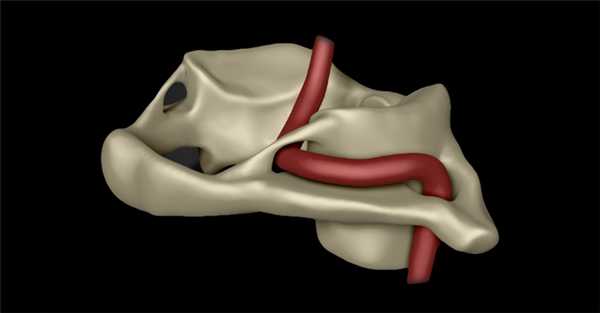

(Справа) На трехмерной реформатированной КТА (вид сзади) визуализируются позвоночные артерии: левая (доминирующая) и правая (меньшего размера, недоминирующая). Обе артерии ограничены замкнутым костным мостиком вдоль верхнего края дуги С1.

• КТА:

о Позвоночная артерия в костном туннеле

о В костном туннеле проходит ипсилатеральная позвоночная артерия